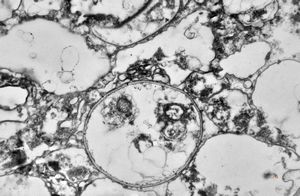

M,50y. | Pneumocystis carinii